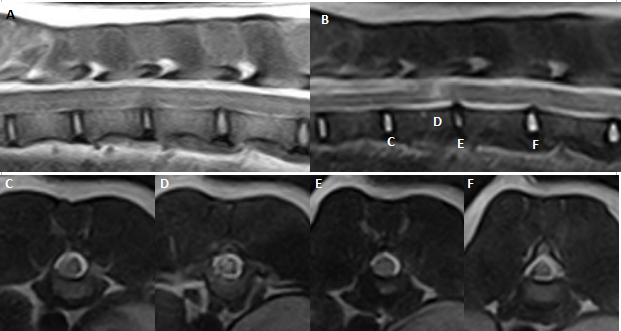

Art685_Fig9